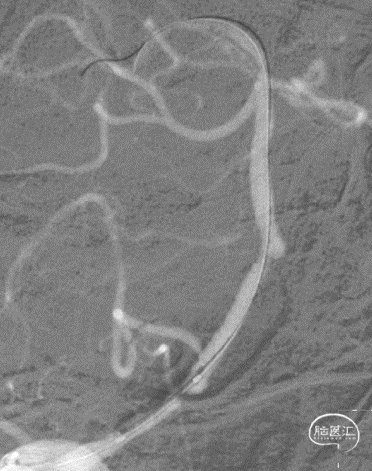

病变情况分析:右桡动脉穿刺,置6F桡动脉鞘管,5F多功能导管在泥鳅导丝辅助下脑血管造影提示:右椎动脉V4段重度狭窄(约90%)。

泥鳅导丝携5F 115cm颅内支撑导管,至右椎动脉V2段。

在颅内支撑导管支撑下,将0.014'' 300cm微导丝,通过狭窄节段将其放置在基底动脉中段。将2.0mm*10mm球囊打起预扩狭窄部位,然后更换赛诺神畅 颅内药物洗脱支架NOVA DES® 2.5*10mm延微导丝顺利通过狭窄节段,再次造影见定位准确,缓慢扩张球囊释放支架。